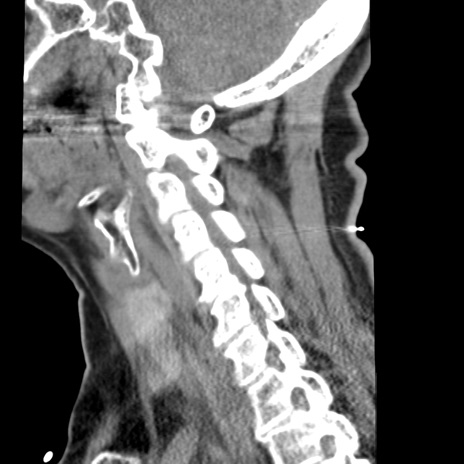

症例50 頚椎CT(矢状断像)

頚椎CT

横断像

冠状断像

【症例】60歳代女性

【主訴】後頭部〜右後頸部にかけての痛み

【現病歴】本日飲食店でコーヒーを飲んでいたところ、突然後頭部〜右後頸部にかけて痛みが出現し、右上肢の感覚障害を伴ったため救急要請。

【身体所見】脳神経学的に明らかな異常所見を認めず。右上肢に軽度の感覚障害あり。

異常所見と診断は?